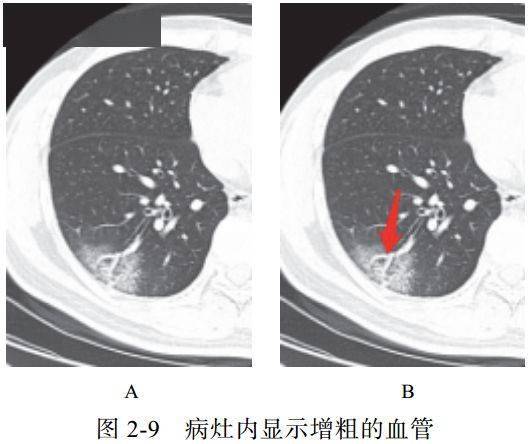

(九)血管增粗征

在亚实性病灶内部清晰显示血管走行,部分血管管径增粗,甚至比近端更粗

可能提示病理改变为血管周围间质水肿,并非血管内径增粗(图 2-9)